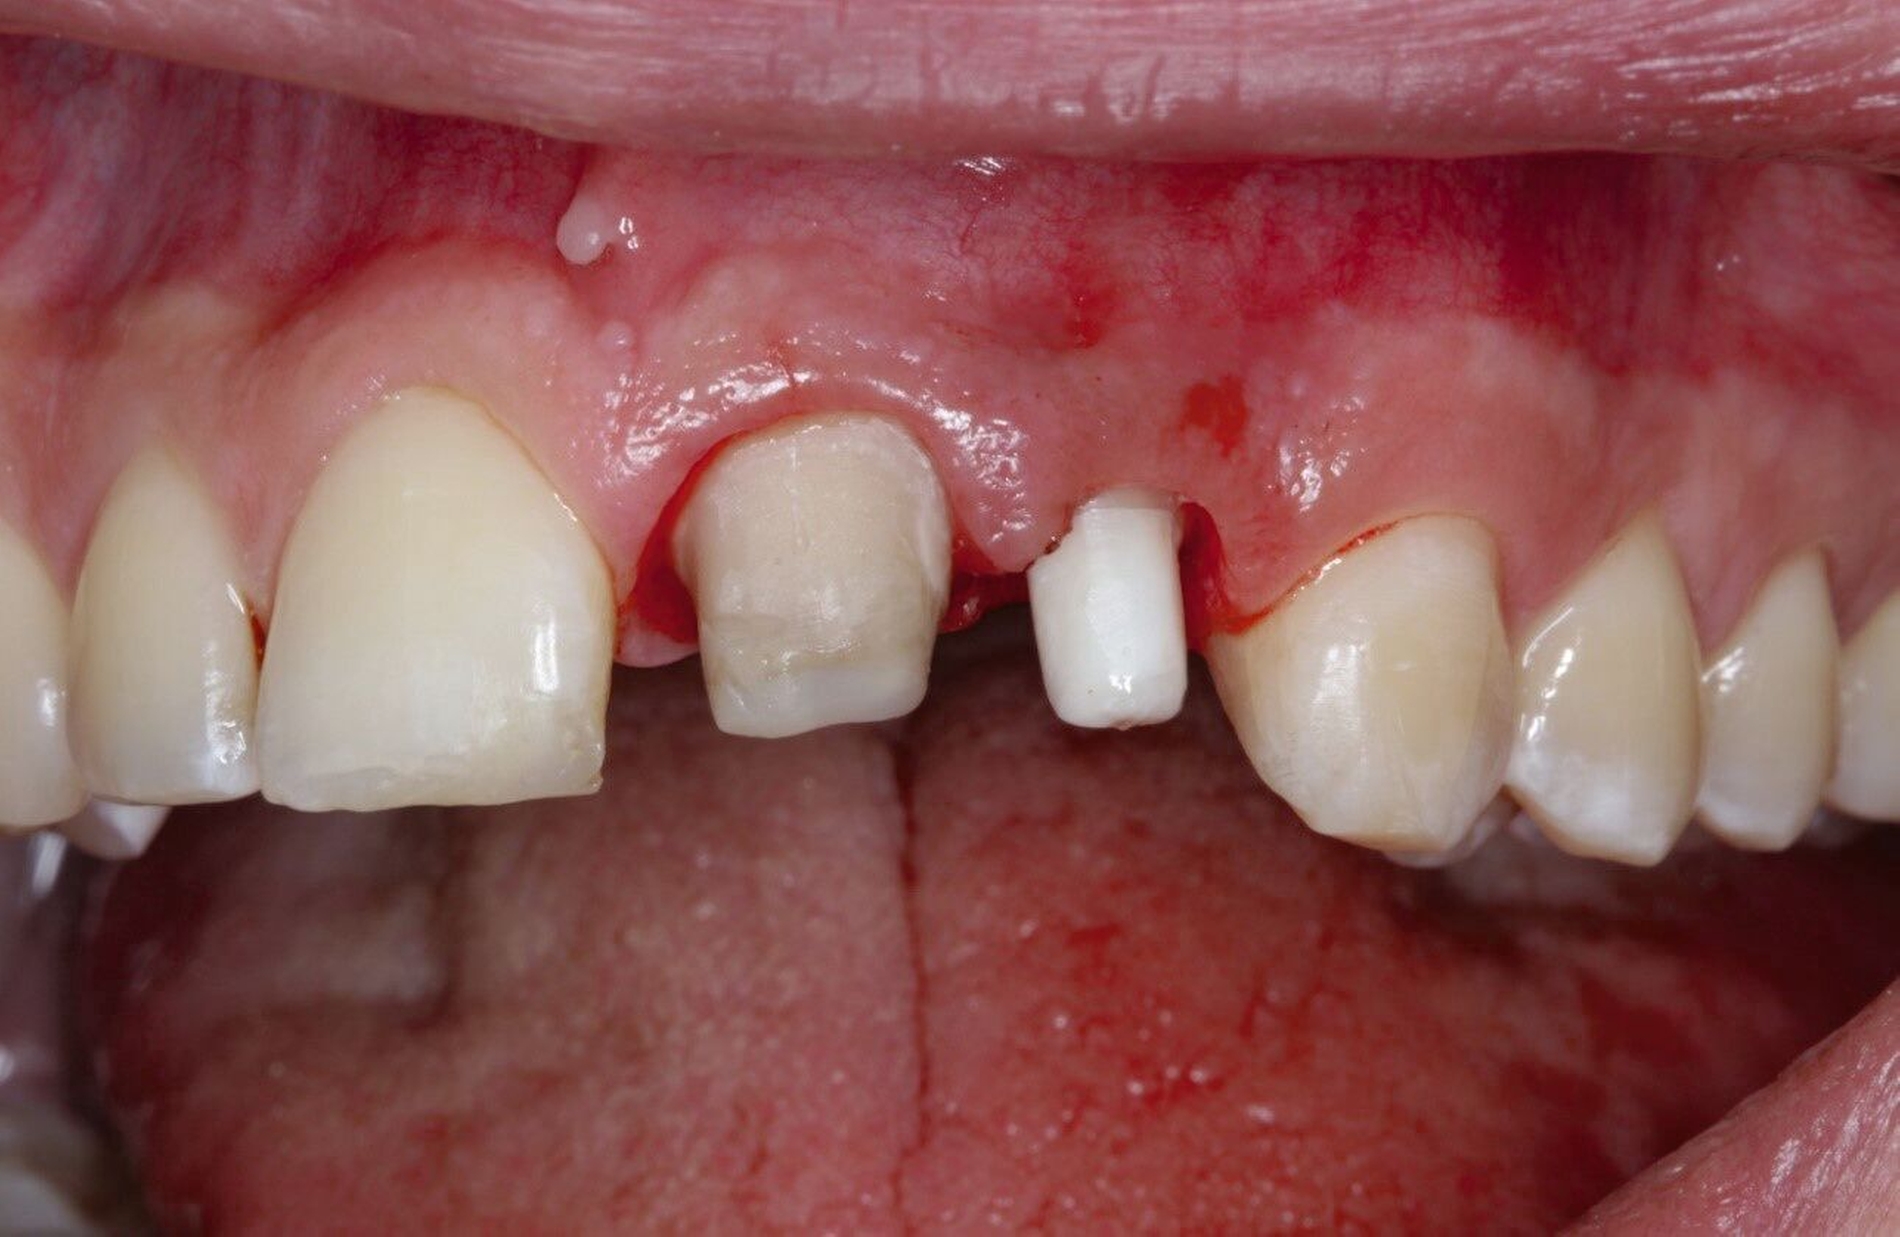

Ein 22-jähriger Patient stellte sich im Februar 2020 im zahnärztlichen Notdienst der Klinik für Zahn-, Mund- und Kieferkrankheiten Mainz vor. Aufgrund einer Synkope war er mit dem Oberkiefer auf den Rand einer Badewanne gestürzt. Intraoral zeigte sich der Zahn 12 mit einer Schmelz-Dentin-Fraktur ohne Pulpabeteiligung (unkomplizierte Kronenfraktur), der Zahn 11 mit einer Kronen-Wurzel-Fraktur mit Pulpabeteiligung und der Zahn 21 mit einer Schmelz-Dentin-Fraktur mit Pulpabeteiligung (komplizierte Kronenfraktur). Die Zähne zeigten keine erhöhten Lockerungsgrade oder Dislokationen (Abbildung 2). Herausfordernd für die weitere Versorgung war der Frakturverlauf an Zahn 11, an dem die Frakturkante palatinal tief subgingival und mesio-palatinal auch subkrestal lag. Röntgenologisch konnte die klinisch gestellte Verdachtsdiagnose bestätigt und eine Wurzelfraktur ausgeschlossen werden (Abbildung 3).

Im Rahmen der Notfallversorgung wurden die Dentinwunden an Zahn 12 provisorisch mit Glasionomerzement verschlossen und die Zähne 11 und 21 mit Kalziumhydroxid-Präparaten direkt überkappt und anschließend dentinadhäsiv versiegelt. Im Verlauf wurde ein Wax-Up für direkte provisorische Kompositaufbauten hergestellt (Abbildung 4). Zur semipermanenten Versorgung musste per Elektrotom mesial und palatinal an Zahn 11 Gingiva exzidiert werden, um einen adäquaten Zugang und eine suffiziente Kontrolle des Arbeitsfeldes zu gewährleisten (Abbildung 5). Durch die direkte provisorische Restauration war der Patient sofort versorgt. Er konnte ohne größere Beeinträchtigung am sozialen Leben teilnehmen und hatte so Zeit für die endgültige Therapieentscheidung (Abbildungen 6 bis 8).